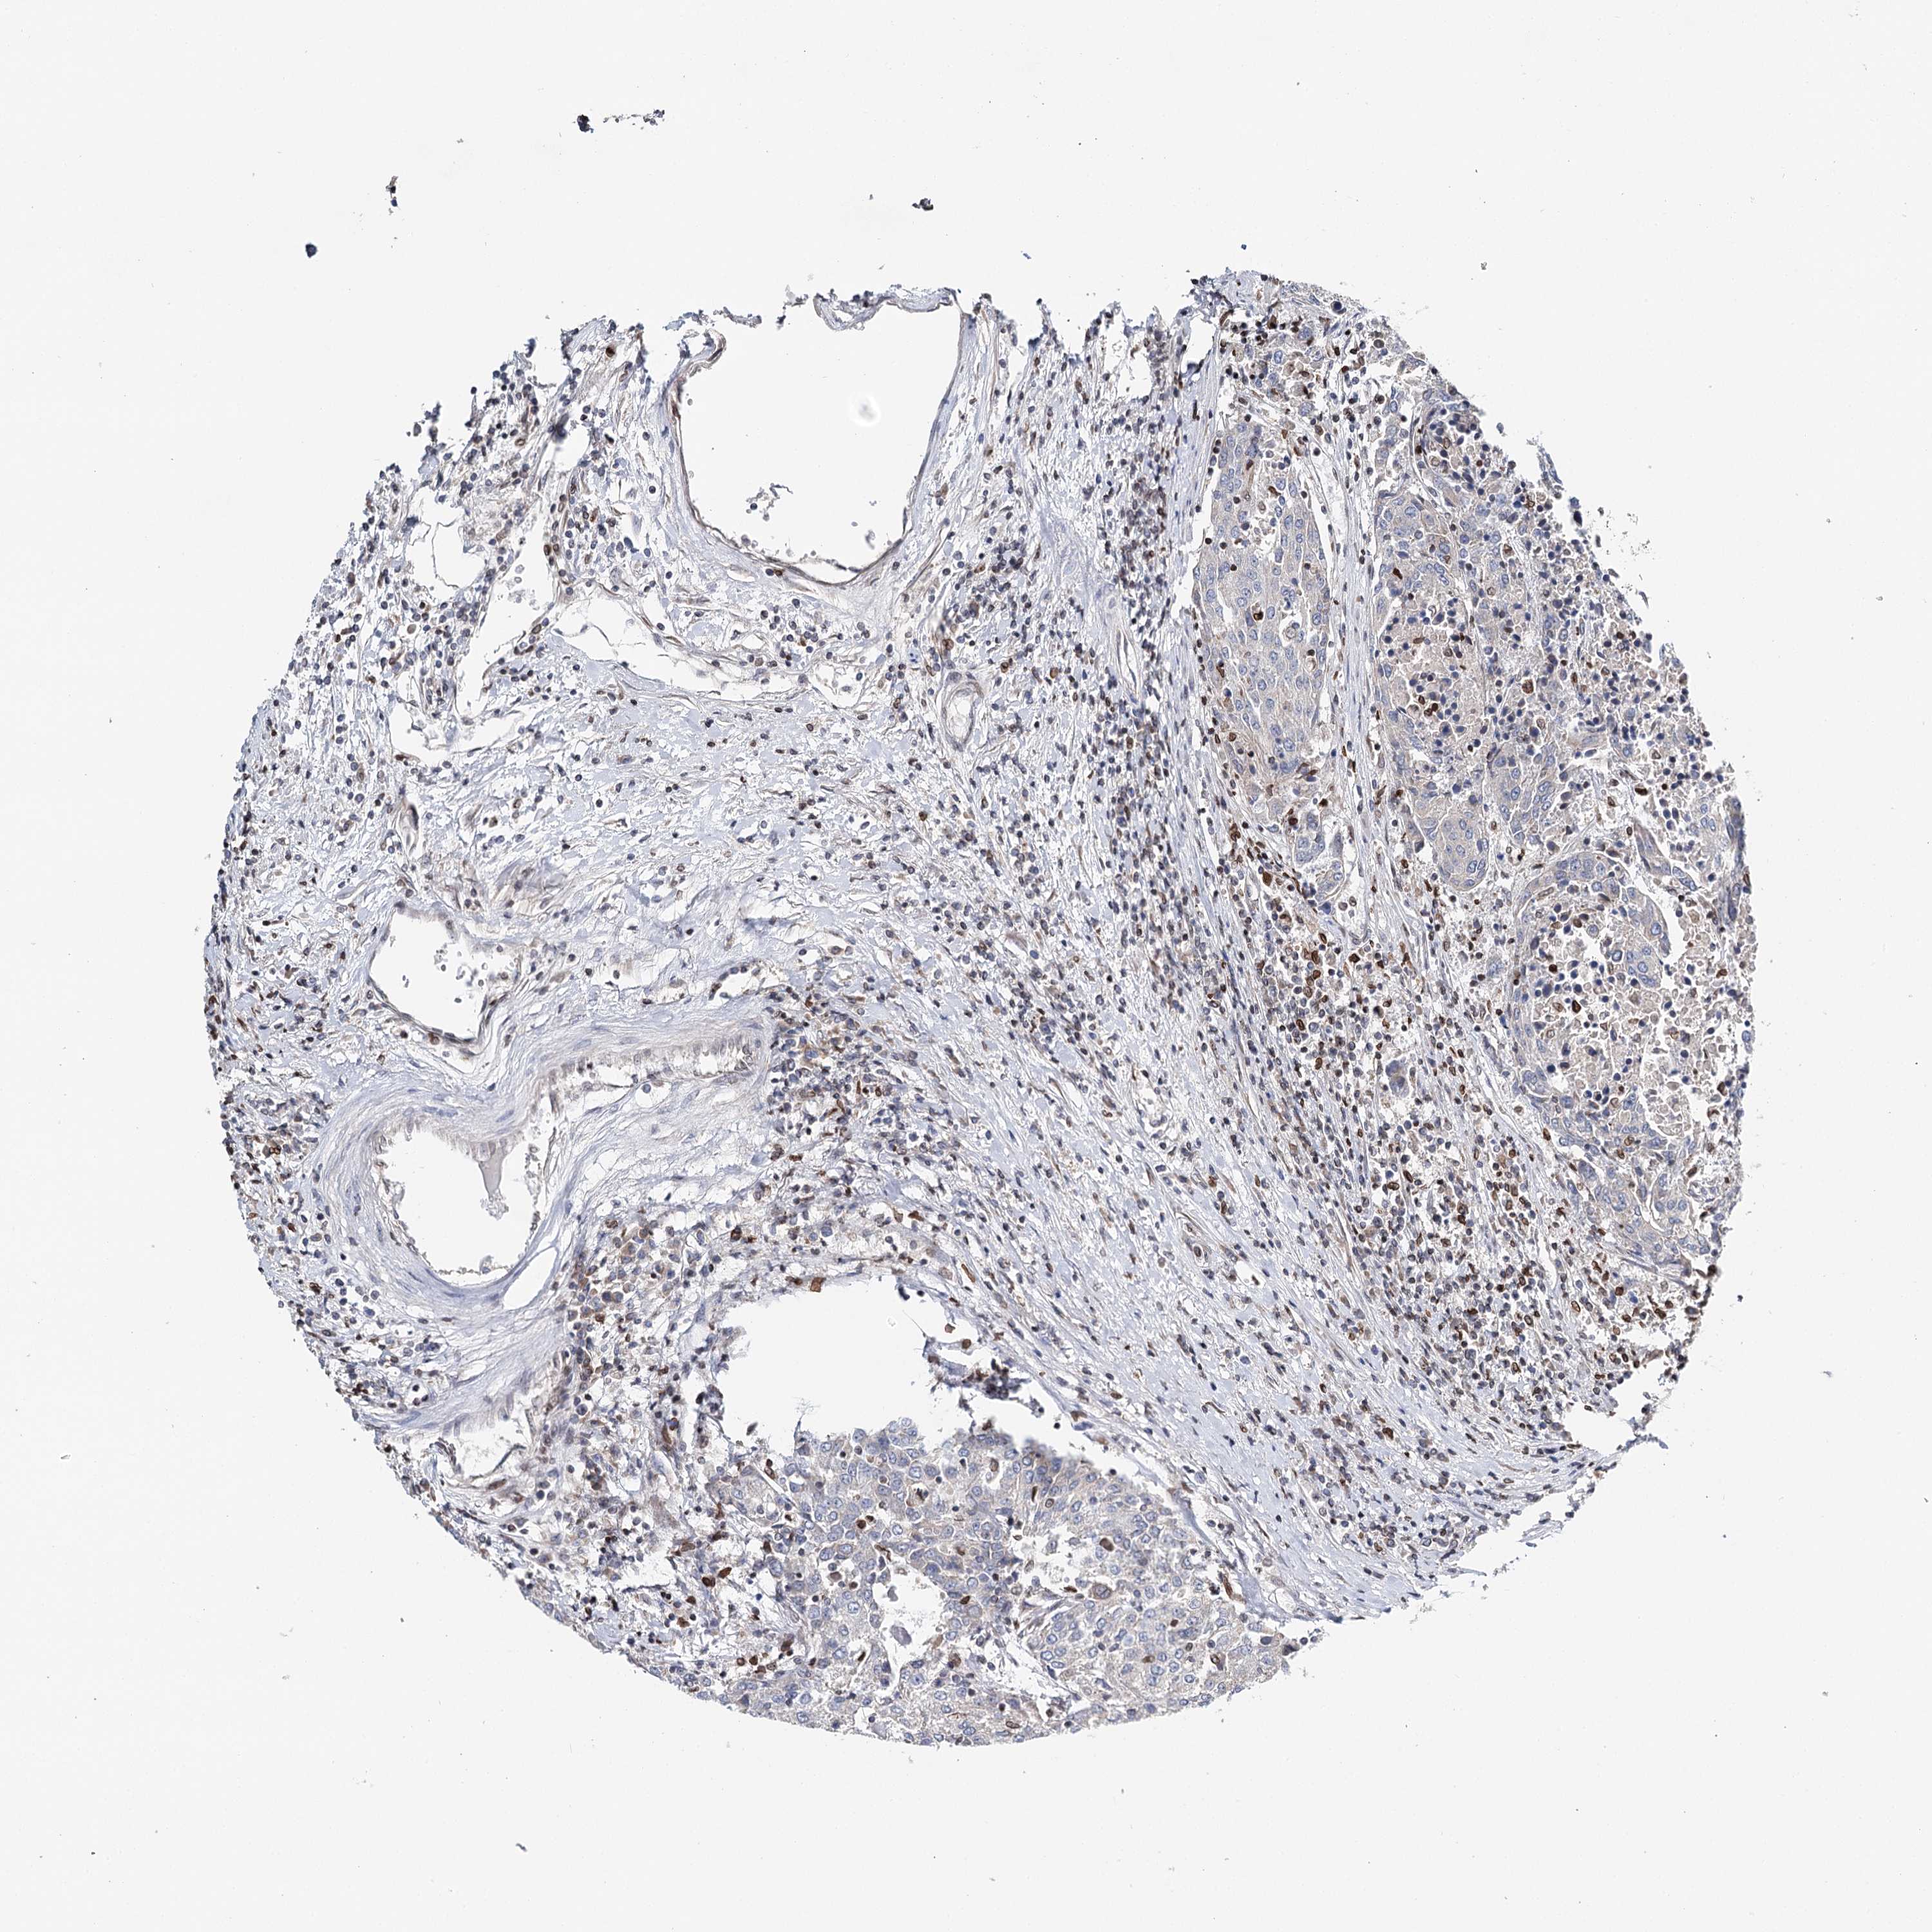

UROTHELIAL CANCER - Protein expressioni

A mouse-over function shows sample information and annotation data. Click on an image to view it in a full screen mode. Samples can be filtered based on level of antibody staining by selecting one or several of the following categories: high, medium, low and not detected. The assay and annotation is described here.

Note that samples used for immunohistochemistry by the Human Protein Atlas do not correspond to samples in the TCGA dataset.

Antibody stainingi

Antibody staining in the annotated cell types in the current human tissue is reported as not detected, low, medium, or high, based on conventional immunohistochemistry profiling in selected tissues. This score is based on the combination of the staining intensity and fraction of stained cells.

Each image is clickable and will lead to virtual microscopy that enables deeper exploration of all samples and also displays staining intensity scores, fraction scores and subcellular localization as well as patient and tissue information for each sample.

Antibody HPA037786

Antibody HPA038034

Antibody HPA038867

Antibody HPA038868

Staining

High

Medium

Low

Not detected

Intensity

Strong

Moderate

Weak

Negative

Quantity

>75%

75%-25%

<25%

None

Location

Nuclear

Cytoplasmic/membranous

Cytoplasmic/membranous,nuclear

Urothelial carcinoma, High grade

Urothelial carcinoma, Low grade

Urothelial carcinoma, NOS